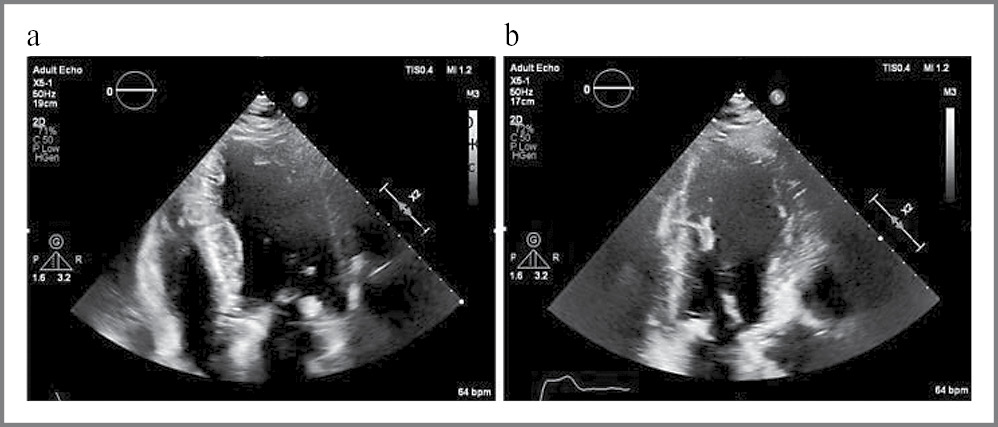

В середине декабря 2022 г. у пациента появились одышка при минимальной физической нагрузке, симметричные отеки голеней, по поводу чего проводилась симптоматическая диуретическая терапия. По данным ЭхоКГ по месту жительства заподозрена зона гипоакинезии верхушечных сегментов ЛЖ с формированием пристеночного тромба, пациент направлен на обследование в ФГБУ «НМИЦK им. акад. Е.И. Чазова». При проведении ЭхоКГ в ФГБУ «НМИЦK им. акад. Е.И. Чазова» выявлено расширение левых камер сердца: индекс конечного диастолического объема ЛЖ – 83,8 мл/м2, индекс объема левого предсердия (ЛП) – 51 мл/м2. Зон нарушения локальной сократимости не выявлено, отмечалось асинхронное движение МЖП, обусловленное БЛНПГ. Тромб в полости ЛЖ не определялся. Подтверждена выраженная гипертрофия с неоднородной эхогенностью миокарда ЛЖ (рис. 5) без признаков обструкции выносящего тракта ЛЖ.

Рис. 5. ЭхоКГ. Слева – апикальная четырехкамерная позиция с выраженной гипертрофией миокарда ЛЖ. Справа – апикальная трехкамерная позиция с кальцинозом АК.

Fig. 5. Echocardiography. On the left: the apical four-chamber with pronounced hypertrophy of the LV myocardium. On the right: the apical three-chamber with AV calcification.

Вместе с этим выявлен стеноз устья аорты с максимальным систолическим градиентом давления на аортальном клапане (мГДсАК) 90 мм рт. ст., средним градиентом давления 54 мм рт. ст., площадью отверстия по уравнению непрерывности потока 0,9–1,0 см2, что соответствует тяжелой степени стеноза устья аорты. Также отмечалась аортальная регургитация (АР) 2–3-й степени (рис. 6).